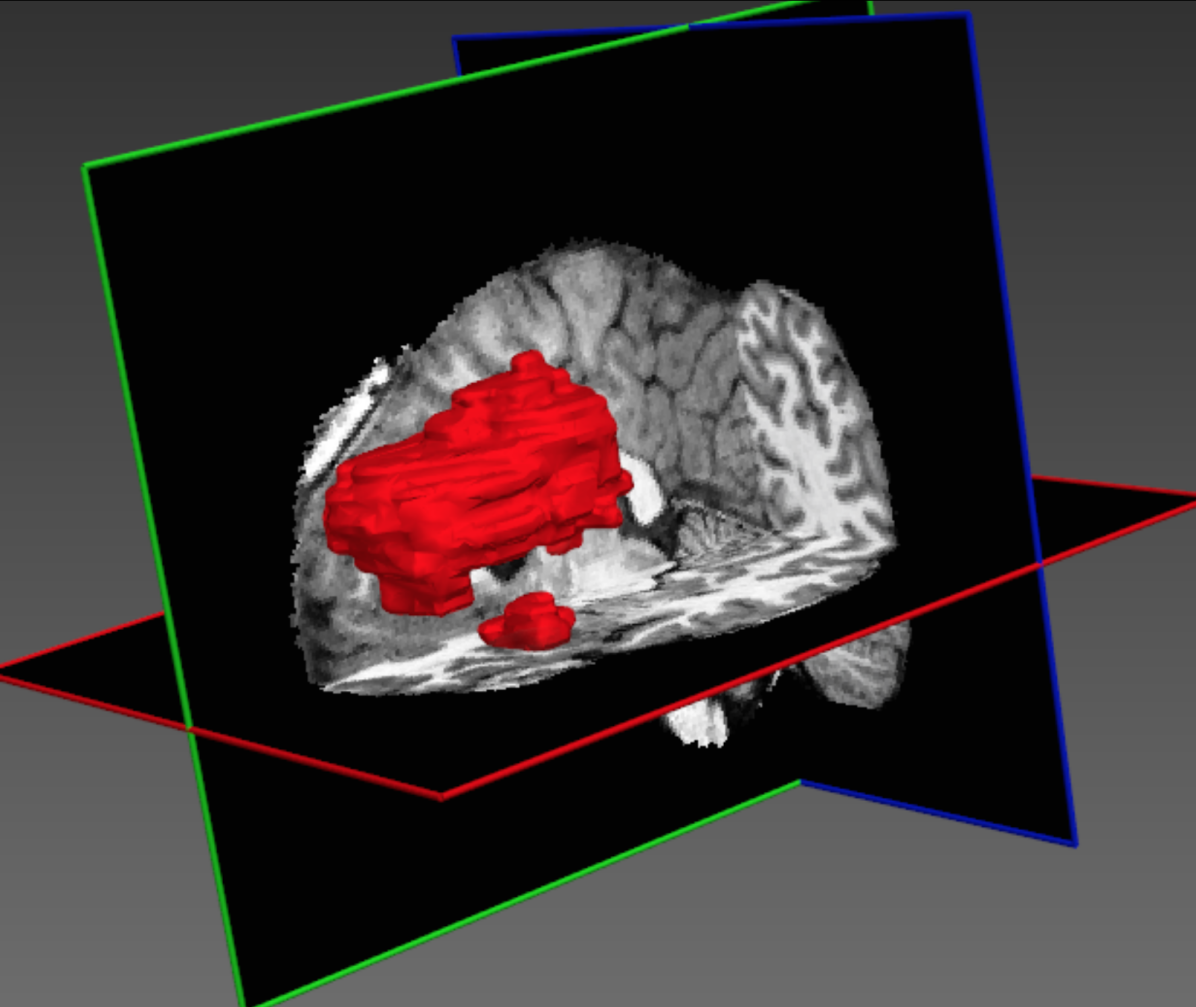

Refer to caption

Figure 3: Consider a network with a 2D receptive field of 32superscript323^{2} (for illustration) densely-applied on the depicted lesion-centred image segments of size 72superscript727^{2} or 92superscript929^{2}. Relatively more background (green) is captured by larger segments and around smaller lesions.

An appealing consequence of this scheme is that the sampling of input segments provides a flexible and automatic way to balance the distribution of training samples from different segmentation classes which is an important issue that directly impacts the segmentation accuracy. Specifically, we build the training batches by extracting segments from the training images with 50% probability being centred on a foreground or background voxel, alleviating class-imbalance. Note that the predicted voxels V𝑉V in a segment do not have to be of the same class, something that occurs when a segment is sampled from a region near class boundaries (Fig. 3). Hence, the sampling rate of the proposed hybrid method adjusts to the true distribution of the segmentation task’s classes. Specifically, the smaller a labelled object, the more background voxels will be captured within segments centred on the foreground voxel. Implicitly, this yields a balance between sensitivity and specificity in the case of binary segmentation tasks. In multi-class problems, the rate at which different classes are captured within a segment centred on foreground reflects the real relative distribution of the foreground classes, while adjusting their frequency relatively to the background.